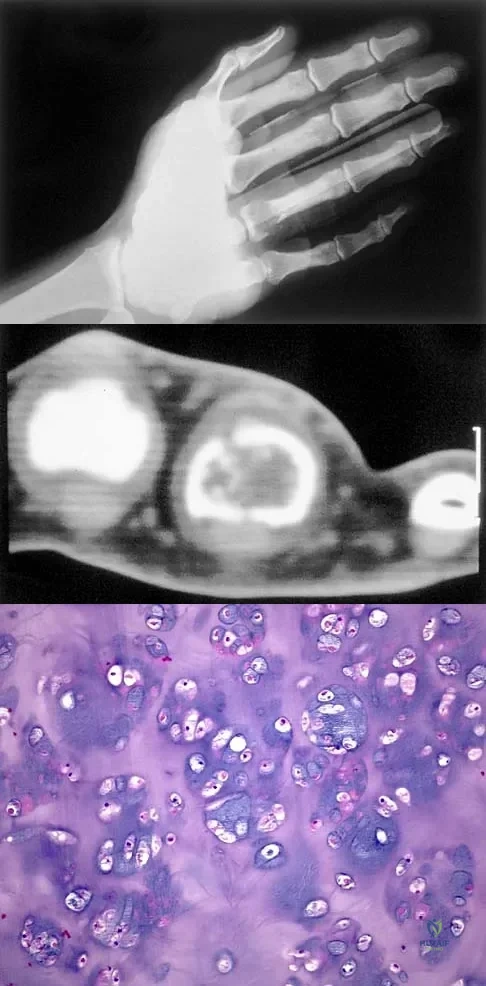

A 30-year-old woman has pain in her right hand. The radiograph, CT scan, and biopsy specimen are seen in Figures 38a through 38c. What is the most likely diagnosis?

Explanation

A 15-year-old girl reports a 6-month history of activity-related knee pain and swelling. A radiograph, MRI scan, and biopsy specimen are shown in Figures 21a through 21c. What is the most likely diagnosis?

Explanation

Figures 19a and 19b show the AP and lateral radiographs of an 18-year-old man who has had knee pain for 3 months. Figure 19c shows a histopathologic photomicrograph of the biopsy specimen. Which of the following factors is most likely to affect his survival?

Explanation